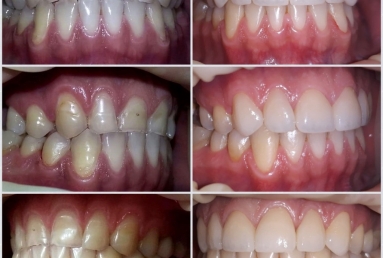

This patient has advanced dental abrasion due to bruxism ( clenching the teeth during the night). this is why the bite is modified and the frontal teeth are shorter. First stage of the treatment is wearing a night guard to relax the muscles and the temporo-mandibular jaw.

Then fixed orthodontic treatment is set for almost 2 years, so moving the teeth a new more favorable position is obtained to create space for veneers. After wax up a mock up is done for provisional veneers and the new occlusion is tested.

The final porcelain veneers for all frontal maxillary teeth are completed with tooth whitening and changing some composite fillings in lower frontals. On the lower left side a dental implant is inserted, on the upper right side external sinus lift is done. the treatment will be finalised with another upper implant, then two crowns on implants.